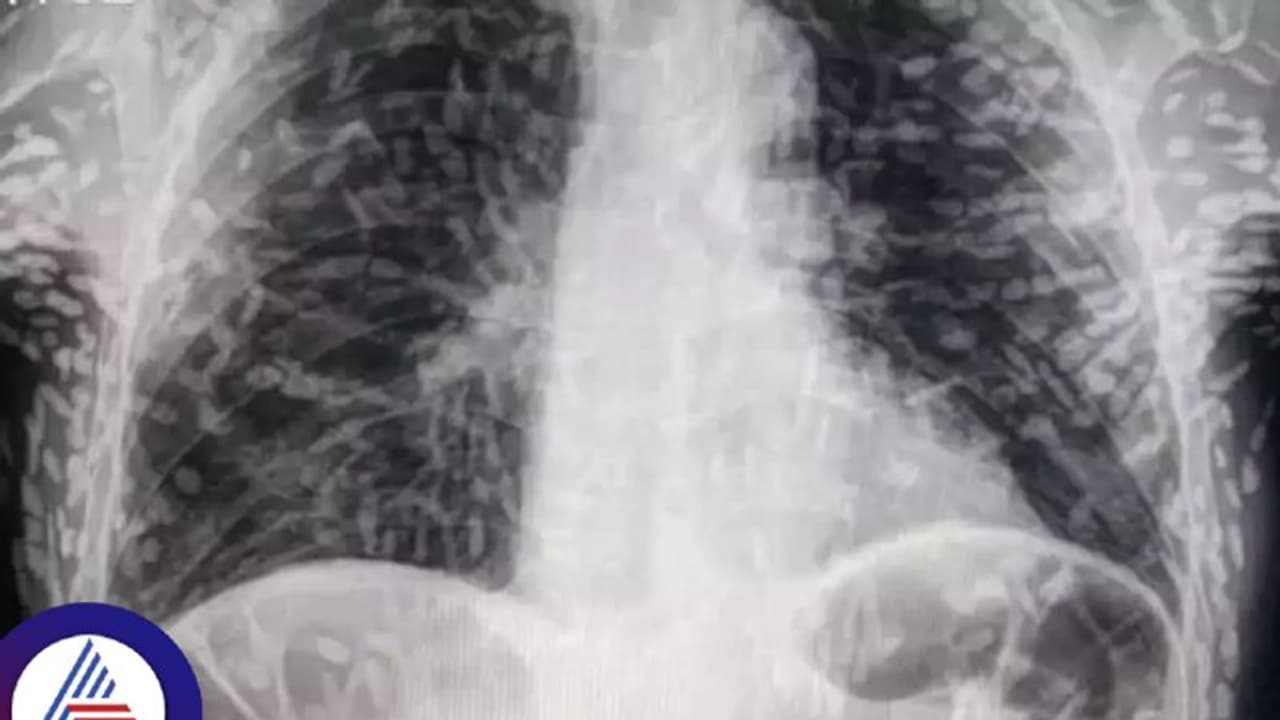

ವಿಪರೀತ ಕೆಮ್ಮೆಂದು ಆಸ್ಪತ್ರೆಗೆ ಹೋದ ವ್ಯಕ್ತಿಯ ದೇಹದೊಳಗೆ ಡಜನ್ಗಟ್ಟಲೆ ಹುಳುಗಳು ಪತ್ತೆಯಾದ ಘಟನೆ ಬ್ರೆಜಿಲ್ನಲ್ಲಿ ನಡೆದಿದೆ. ಟ್ವಿಟರ್ನಲ್ಲಿ ಹಂಚಿಕೊಂಡ ನಂತರ ಸ್ಕ್ಯಾನ್ಗಳ ಫೋಟೋಗಳು ಸೋಷಿಯಲ್ ಮೀಡಿಯಾದಲ್ಲಿ ವೈರಲ್ ಆಗಿವೆ.

ಆರೋಗ್ಯ (Health) ಸರಿಯಿಲ್ಲವೆಂದು ಆಸ್ಪತ್ರೆಗೆ ಬಂದ ರೋಗಿಗೆ ವೈದ್ಯರು ಎಕ್ಸ್-ರೇ ತೆಗೆದಾಗ ಆಘಾತಕಾರಿ ವಿಚಾರ ಪತ್ತೆಯಾಯಿತು. ಬ್ರೆಜಿಲ್ನ ಸಾವೊ ಪಾಲೊದಲ್ಲಿರುವ ದಾಸ್ ಕ್ಲಿನಿಕಾಸ್ ಬೊಟುಕಾಟು ಆಸ್ಪತ್ರೆಯ ಅಭ್ಯಾಸಿ ಡಾ.ವಿಟರ್ ಬೋರಿನ್ ಪಿ. ಡಿ ಸೋಜಾ ಅವರು ಟ್ವಿಟರ್ನಲ್ಲಿ ಹಂಚಿಕೊಂಡ ನಂತರ ಸ್ಕ್ಯಾನ್ಗಳ ಫೋಟೋಗಳು ವೈರಲ್ ಆಯಿತು.

ಪರೀಕ್ಷೆಗಳು ಮತ್ತು ಸ್ಕ್ಯಾನ್ಗಳು ಹಂದಿಮಾಂಸದಿಂದ ದೇಹ (Body)ದಲ್ಲಿ ಹುಳುಗಳು ಉಂಟಾಗಿರುವುದ್ನು ಬಹಿರಂಗಪಡಿಸಿತು. ವ್ಯಕ್ತಿ ಅಂಗಾಂಶದ ಸೋಂಕಿನ ಸಿಸ್ಟಿಸರ್ಕೋಸಿಸ್ನಿಂದ ಬಳಲುತ್ತಿರುವುದು ಪರೀಕ್ಷೆಯಿಂದ ತಿಳಿದುಬಂತು. ಇದು ಸಾಮಾನ್ಯವಾಗಿ ಆಹಾರ (Food) ಸೇವನೆಯಿಂದ ಅಥವಾ ಮಾನವನ ಮಲದಿಂದ ಟೇಪ್ ವರ್ಮ್ಗಳ ಮೊಟ್ಟೆಗಳಿಂದ ಕಲುಷಿತಗೊಂಡ ನೀರನ್ನು ಕುಡಿಯುವುದರಿಂದ ಉಂಟಾಗುತ್ತದೆ ಎಂದು ರೋಗ ನಿಯಂತ್ರಣ ಮತ್ತು ತಡೆಗಟ್ಟುವಿಕೆ ಕೇಂದ್ರಗಳು (CDC) ಹೇಳುತ್ತದೆ: